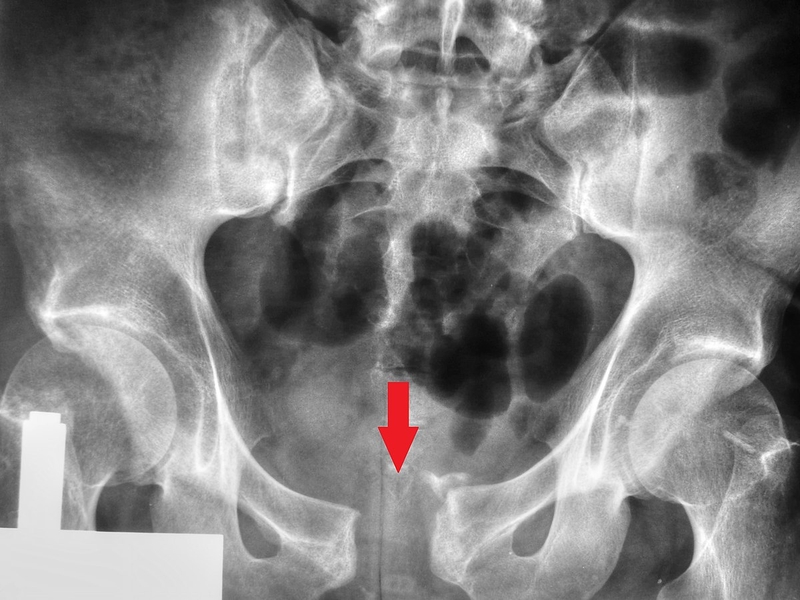

Xương ngành ngồi mu là một phần của khung xương chậu với chức năng chính là nâng đỡ toàn bộ trong lượng của cơ thể cũng như bảo vệ nội tạng vùng chậu. Gãy xương ngành ngồi mu là chấn thương tương đối phổ biến, do đó rất nhiều người quan tâm rằng liệu gãy xương ngành ngồi mu bao lâu mới lành?

Tình trạng gãy xương ngành ngồi mu

Dưới đây chính là một số biến chứng có thể xảy ra do tình trạng gãy xương ngành ngồi mu:

Qua bài viết dưới đây của chúng tôi, chắc hẳn bạn đã biết gãy xương ngành ngồi mu bao lâu mới lành? rồi chứ! Đây là loại chấn thương nguy hiểm có thể làm tổn thương đến các cơ, dây thần kinh và mạch máu xung quanh trong vùng chậu. Do đó, người bệnh cần được đưa đến bệnh viện để chẩn đoán và điều trị ngay lập tức.